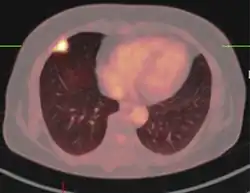

Imaging

The appearance of a tuberculoma on imaging can vary according to the composition and age of the mass. They may appear as either non-caseating or solidly caseating lesions.[20] Initially, tuberculomas appear hypodense on computed tomography (CT) scans with significant surrounding edema.[23][3] The "target sign" is pathognomonic for tuberculoma on CT, with a nodular ring-enhancing mass and central calcification.[24][20] The characteristic ring-enhanced appearance is due to lack of blood supply in the central necrotic core that is visualized with injected contrast.[22] Sometimes a hypodense central area is seen instead of calcification.[25] When considering other potential intracranial masses in a differential diagnosis, such as cysticercosis, pyogenic abscess, and neoplastic lesions, tuberculoma can be identified by its larger size (>2 cm), edema, and irregular border.

Magnetic resonance imaging (MRI) is another useful imaging modality for diagnosing and characterizing of tuberculomas, especially solid caseous necrosis in which 3 zones of varying intensity are seen.[22]